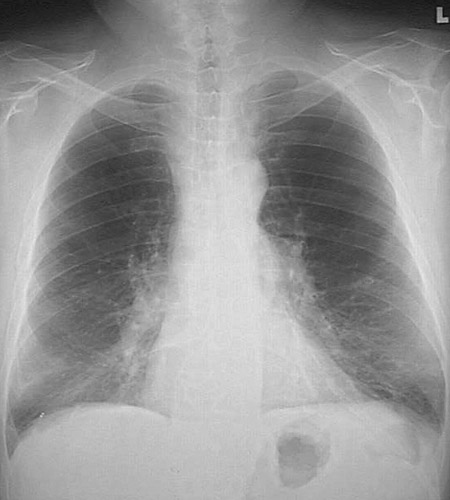

This chest radiograph seen demonstrates

greater lucency

in the upper lobes, along with

flattening of the diaphragmatic leaves

, consistent with centrilobular emphysema.